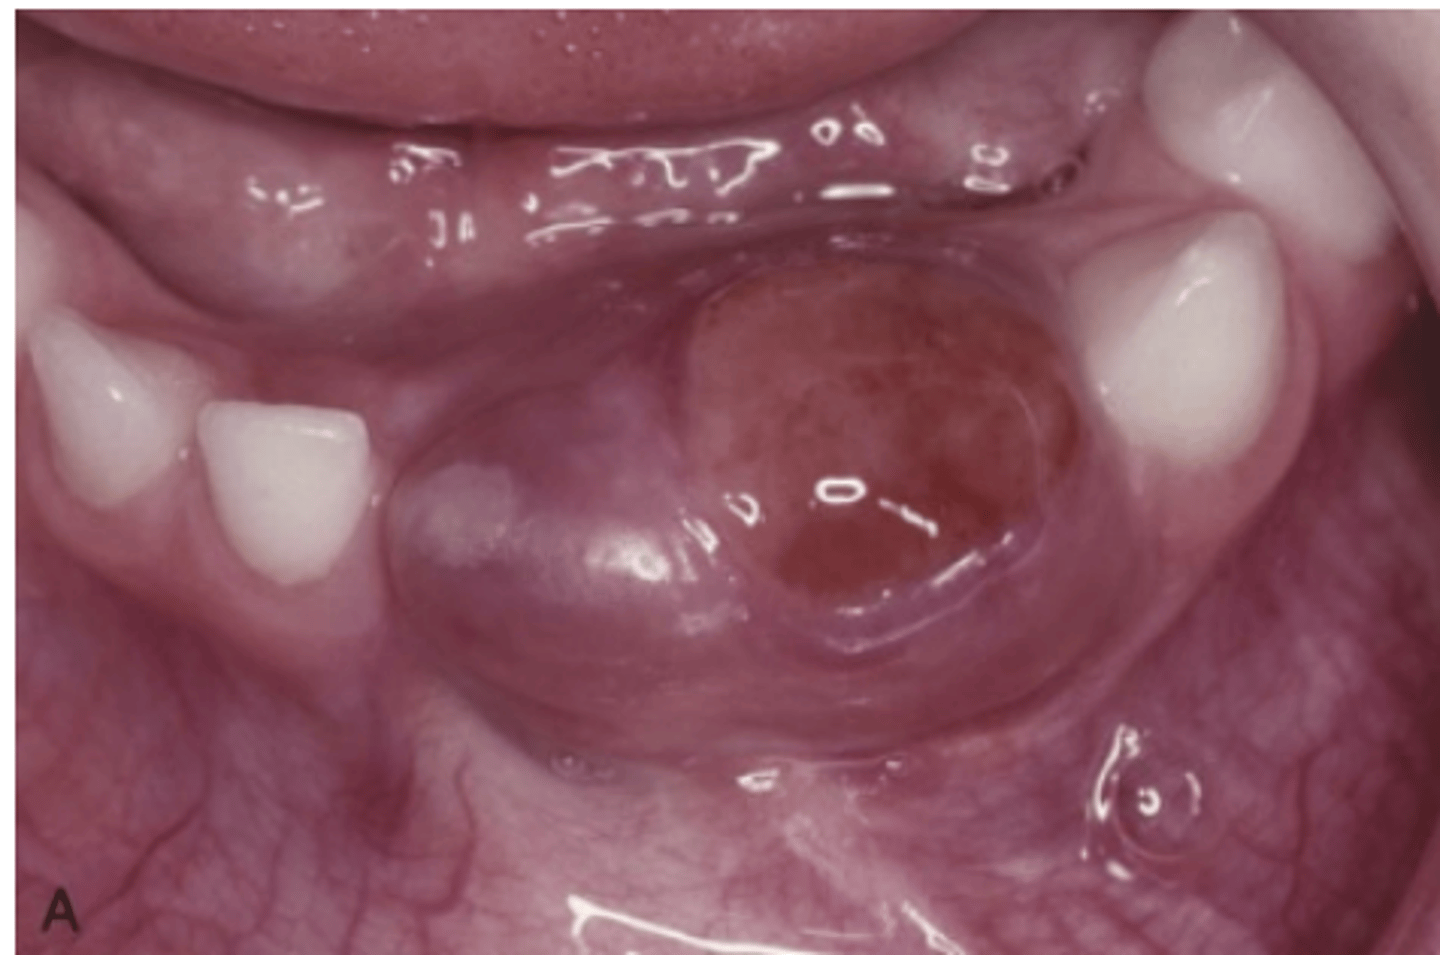

What type of lesion is a Central Giant Cell Granuloma?

An intraosseous lesion.

What is the main controversy surrounding the nature of Central Giant Cell Granuloma?

Whether it is a reactive process or a benign neoplasm.

Where is the most frequent location of Central Giant Cell Granuloma?

70% occur in the mandible

What area of the mouth is Central Giant Cell Granuloma more common?

More common in anterior portion of jaws

What are the two categories of Central Giant Cell Granuloma based on clinical and radiographic features?

Nonaggressive lesions and Aggressive lesions.

What are typical characteristics of nonaggressive Central Giant Cell Granulomas?

Relatively small, few or no symptoms, slow growth, no cortical perforation or root resorption, usually discovered during routine radiographs or due to painless jaw expansion.

How do aggressive Central Giant Cell Granulomas typically present?

Pain, rapid growth, cortical perforation, root resorption, tooth displacement, paresthesia, soft tissue extension, and mucosal ulceration.

What is the treatment for Central Giant Cell Granuloma

Thorough curettage